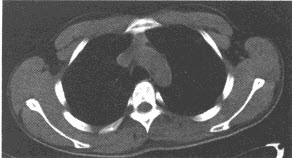

女,43岁,两眼不能完全睁开,全身无力两年余。胸部CT扫描前纵隔内发现肿块,如图,最可能的诊断是()

A:畸胎瘤

B:心包囊肿

C:气管囊肿

D:胸内甲状腺肿

E:胸腺瘤